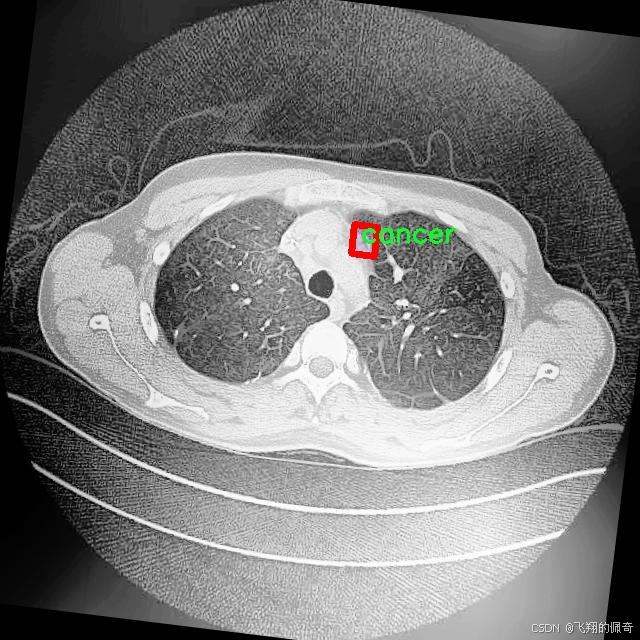

本研究将基于改进的YOLOv8模型,构建一个高效的肺结节图像分割系统。所使用的数据集包含1600幅图像,涵盖了三类重要的病理类型:腺癌、癌症和结节。这些数据不仅为模型的训练提供了丰富的样本,也为后续的模型评估和验证奠定了基础。通过对不同类别的肺结节进行精确分割,研究旨在提高模型在实际应用中的鲁棒性和准确性,进而为临床医生提供更为可靠的辅助诊断工具。

图片效果

在肺结节图像分割的研究中,数据集的选择与构建至关重要。本研究所采用的数据集名为“Lung Nodule Segmentation study”,其设计旨在为改进YOLOv8-seg模型提供高质量的训练数据。该数据集专注于肺部影像中的结节分割,特别是针对不同类型的肺结节进行精确标注,以便于后续的深度学习模型训练和性能评估。

“Lung Nodule Segmentation study”数据集中包含三种主要类别,分别为腺癌(adenocarcinoma)、癌症(cancer)和结节(nodule)。这些类别的选择不仅反映了肺部影像学中的常见病理类型,也为模型的多样性和适应性提供了基础。腺癌作为一种常见的肺癌类型,其在影像学上的表现与其他类型的肺结节有显著差异,因此在数据集中占据了重要地位。癌症这一类别则涵盖了更广泛的病理变化,旨在提高模型对不同癌症类型的识别能力。结节类别则是数据集的核心,主要用于训练模型在图像中准确识别和分割出肺结节的区域。